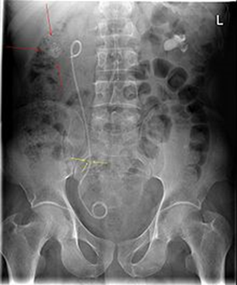

Akut handläggning

• Splint (dubbel JJ-stent) alt Nefrostomi. Vid avstängd pyelit

o Nefrostomi via flank UL-lett, urin ut i påse (förstaval då vi vet att denna funkar, vi får urin ut direkt liksom)

o Splint (bilden) via urinröret till blåsen, sedan till uretärostiet, guidevajer till njure och sedan slang, när vajern dras ut krullar slangen till sig i njure (och även kringla i blåsan) och urin leds ut via denna slang

Vad visar bilden?